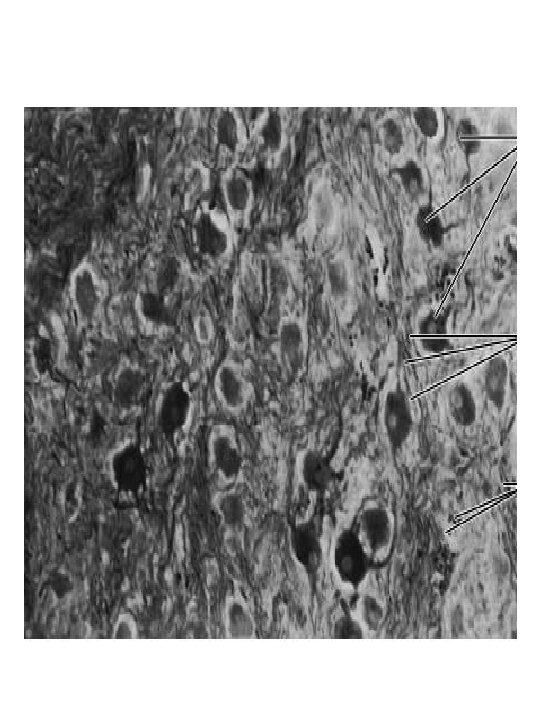

Cytoarchitectonics Brain cortex has 6 layers Pyramidal cells in the 2 nd, 3 rd, 4 th, 5 th layers

Layers of brain cortex 1. Molecular layer 2. Outer granular (10 mkm) 3. Pyramidal (10 -40 mkm) 4. Inner granular layer 5. Ganglionic (120 x 80, Bets, 1874) 6. Multiform layer

Molecular layer: basket cells large stellate cells small stellate cells Purkinje cells layer: Purkinje cells, supporting cells (lophogliocytes) Granular layer: corn cells stellate cells (2 types) horizontal cells